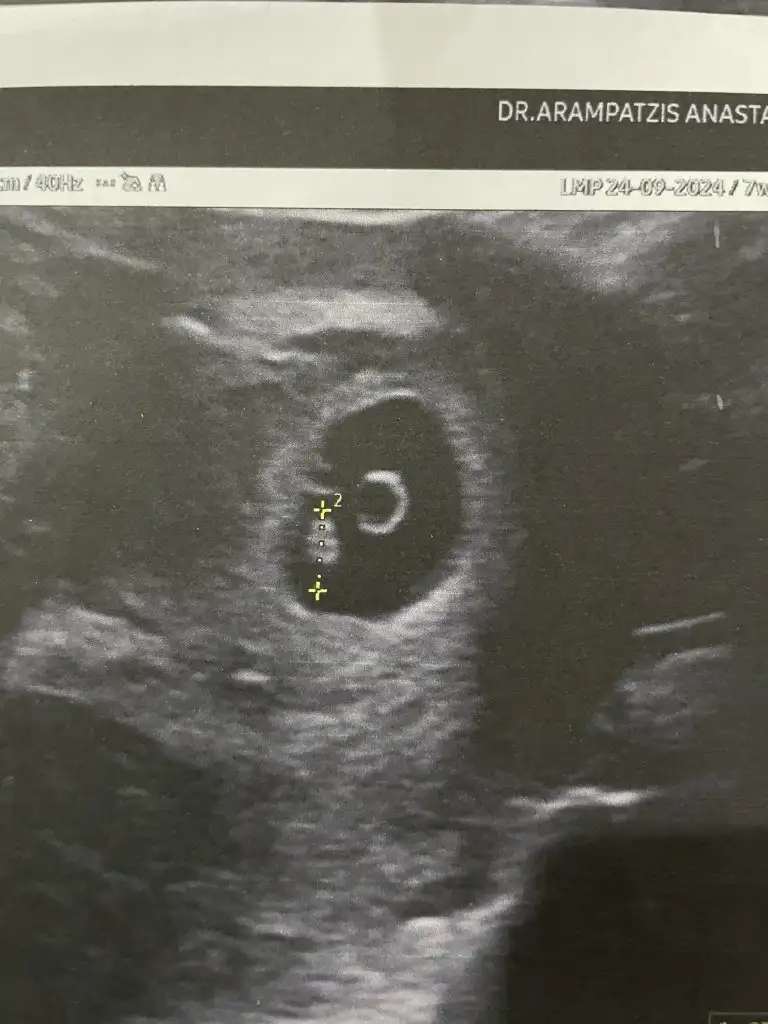

Merhabalar kalp atislarini duyduk cok sukur bebisin

7 haftalik diye biliyordum bir hafta gerideymis 6 haftalik gorunuyor. Dogum 1 temmuzdu simdi 7 temmuz olarak cikiyor

Benim 24 eylul canim keseyi 5 haftalikken gormustum bu aksam kalp atislarinida duyduk cok sukurSon adet tarihiniz nedir acaba ben bügün doktora gittim ama kalp atışı duyamadık maalesef

Anladım neredeyse 10 gün var aramızda benimde son adet tarihi 5 ekim demek benim için daha erken doktor normal dedi inşallah. Bir sorun yokturBenim 24 eylul canim keseyi 5 haftalikken gormustum bu aksam kalp atislarinida duyduk cok sukur

Hayir canim sorun olsa soylerdi ve erken zaten cunku dollenme gecolmus olabiliyor ve hesapladigimiz tarihten kucuk oldugu icin gec basliyor kalp atislari daha zamanin varAnladım neredeyse 10 gün var aramızda benimde son adet tarihi 5 ekim demek benim için daha erken doktor normal dedi inşallah. Bir sorun yoktur